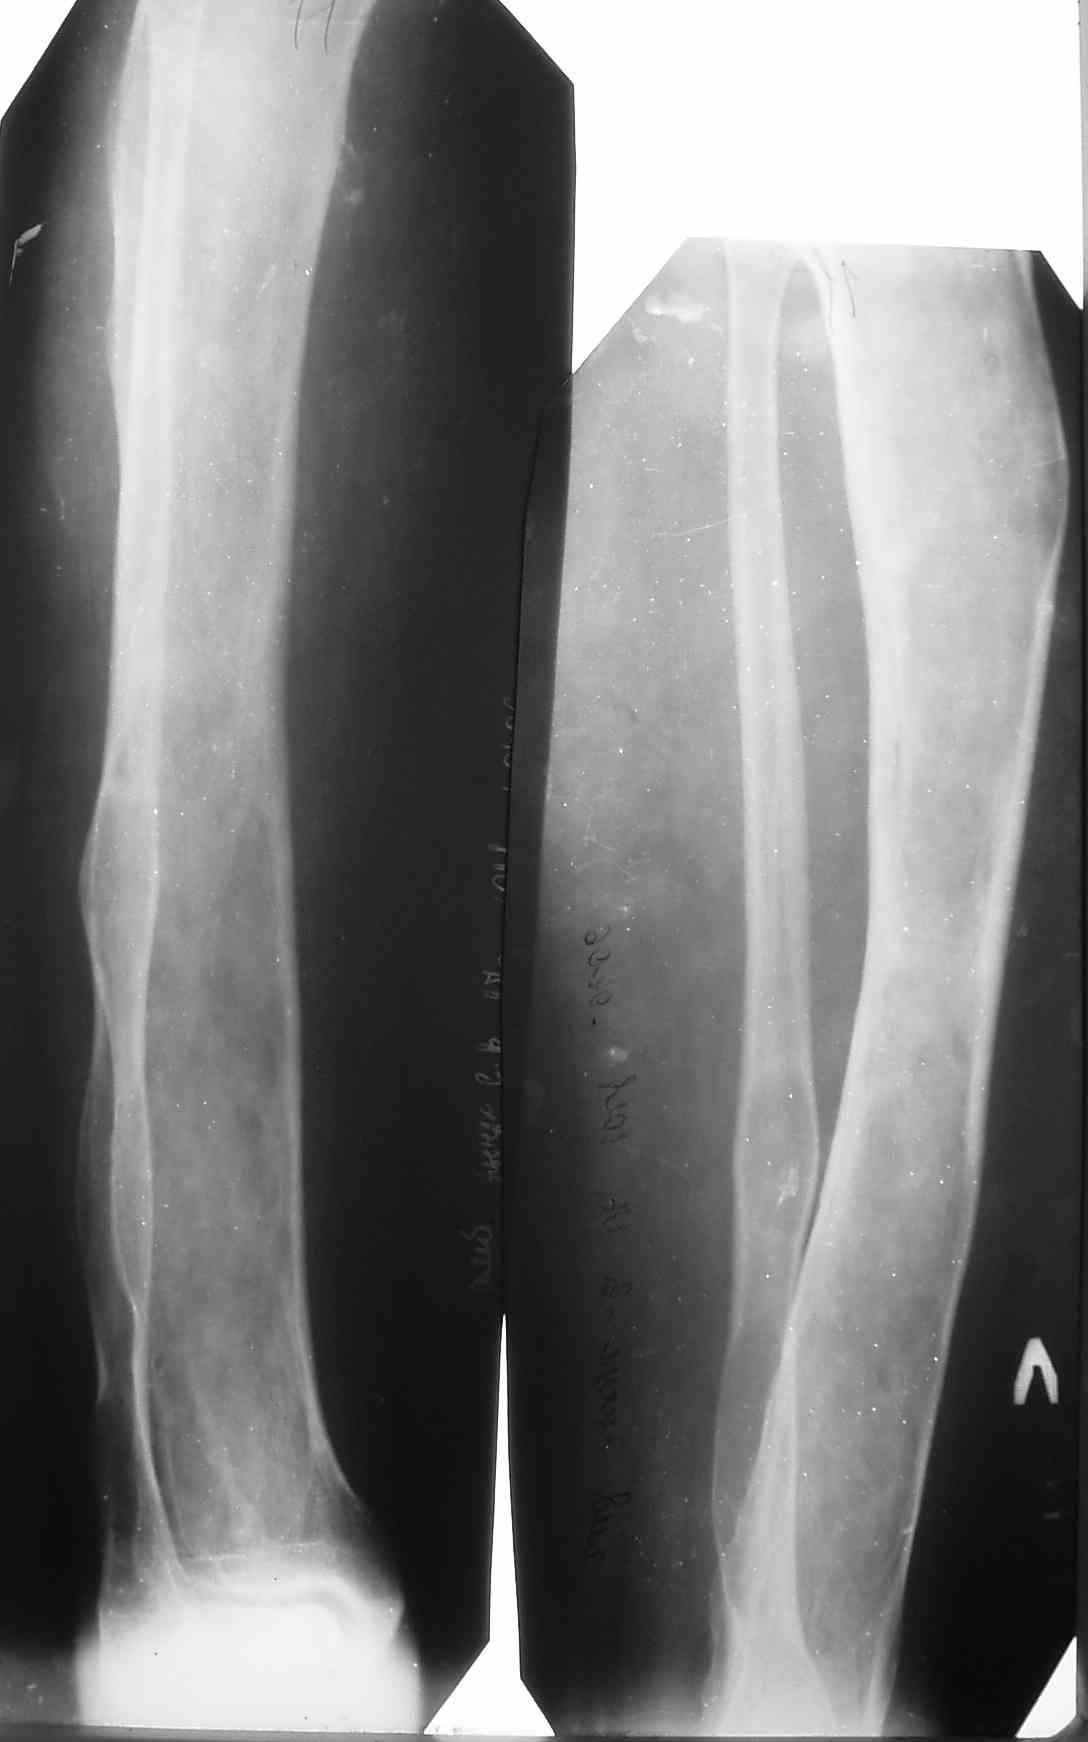

Спасибо за помощь, уважаемый Александр. Буду благодарен за ссылки на литературу. Прямую проекцию выложу. А клиника: веретенообразное утолщение в средней трети голени, безболезненное, не беспокоит. В течение длительного времени ударялась об острый угол дивана этим местом. Три месяца назад заметила вот это самое утолщение на голени, говорит, что с тех пор не увеличилось. С уважением. Алексей.

Здравствуйте уважаемый Алексей!Относительно вашего предварительного диагноза- присоединяюсь к мнению коллег(локализация для гигантоклеточной опухоли не характерна,нет боли,а для гигантоклеточ.опухоли-это главный клинический симптом.Действительно, похоже на болезнь Брайцева,хотя основная масса наблюдений встречается в возрасте до 20 лет.)

Я поддерживаю мнение доктора Odessky Jacob, что это образоавние возможно фиброзная дисплазия. Случай из моей практики - смотри рентгенснимки во вложении. Правда у моего пациента -полиосальная форма и болезнь проявилась в раннем детстве.

Доброго времени суток,уважаемые коллеги.Спасибо за помощь всем, кто откликнулся. Общий алгоритм понятен. Вот прямая проекция, извините за несвоевременность. С уважением, Алексей.

По представленным снимкам наиболее вероятен диагноз "фиброзная дисплазия".